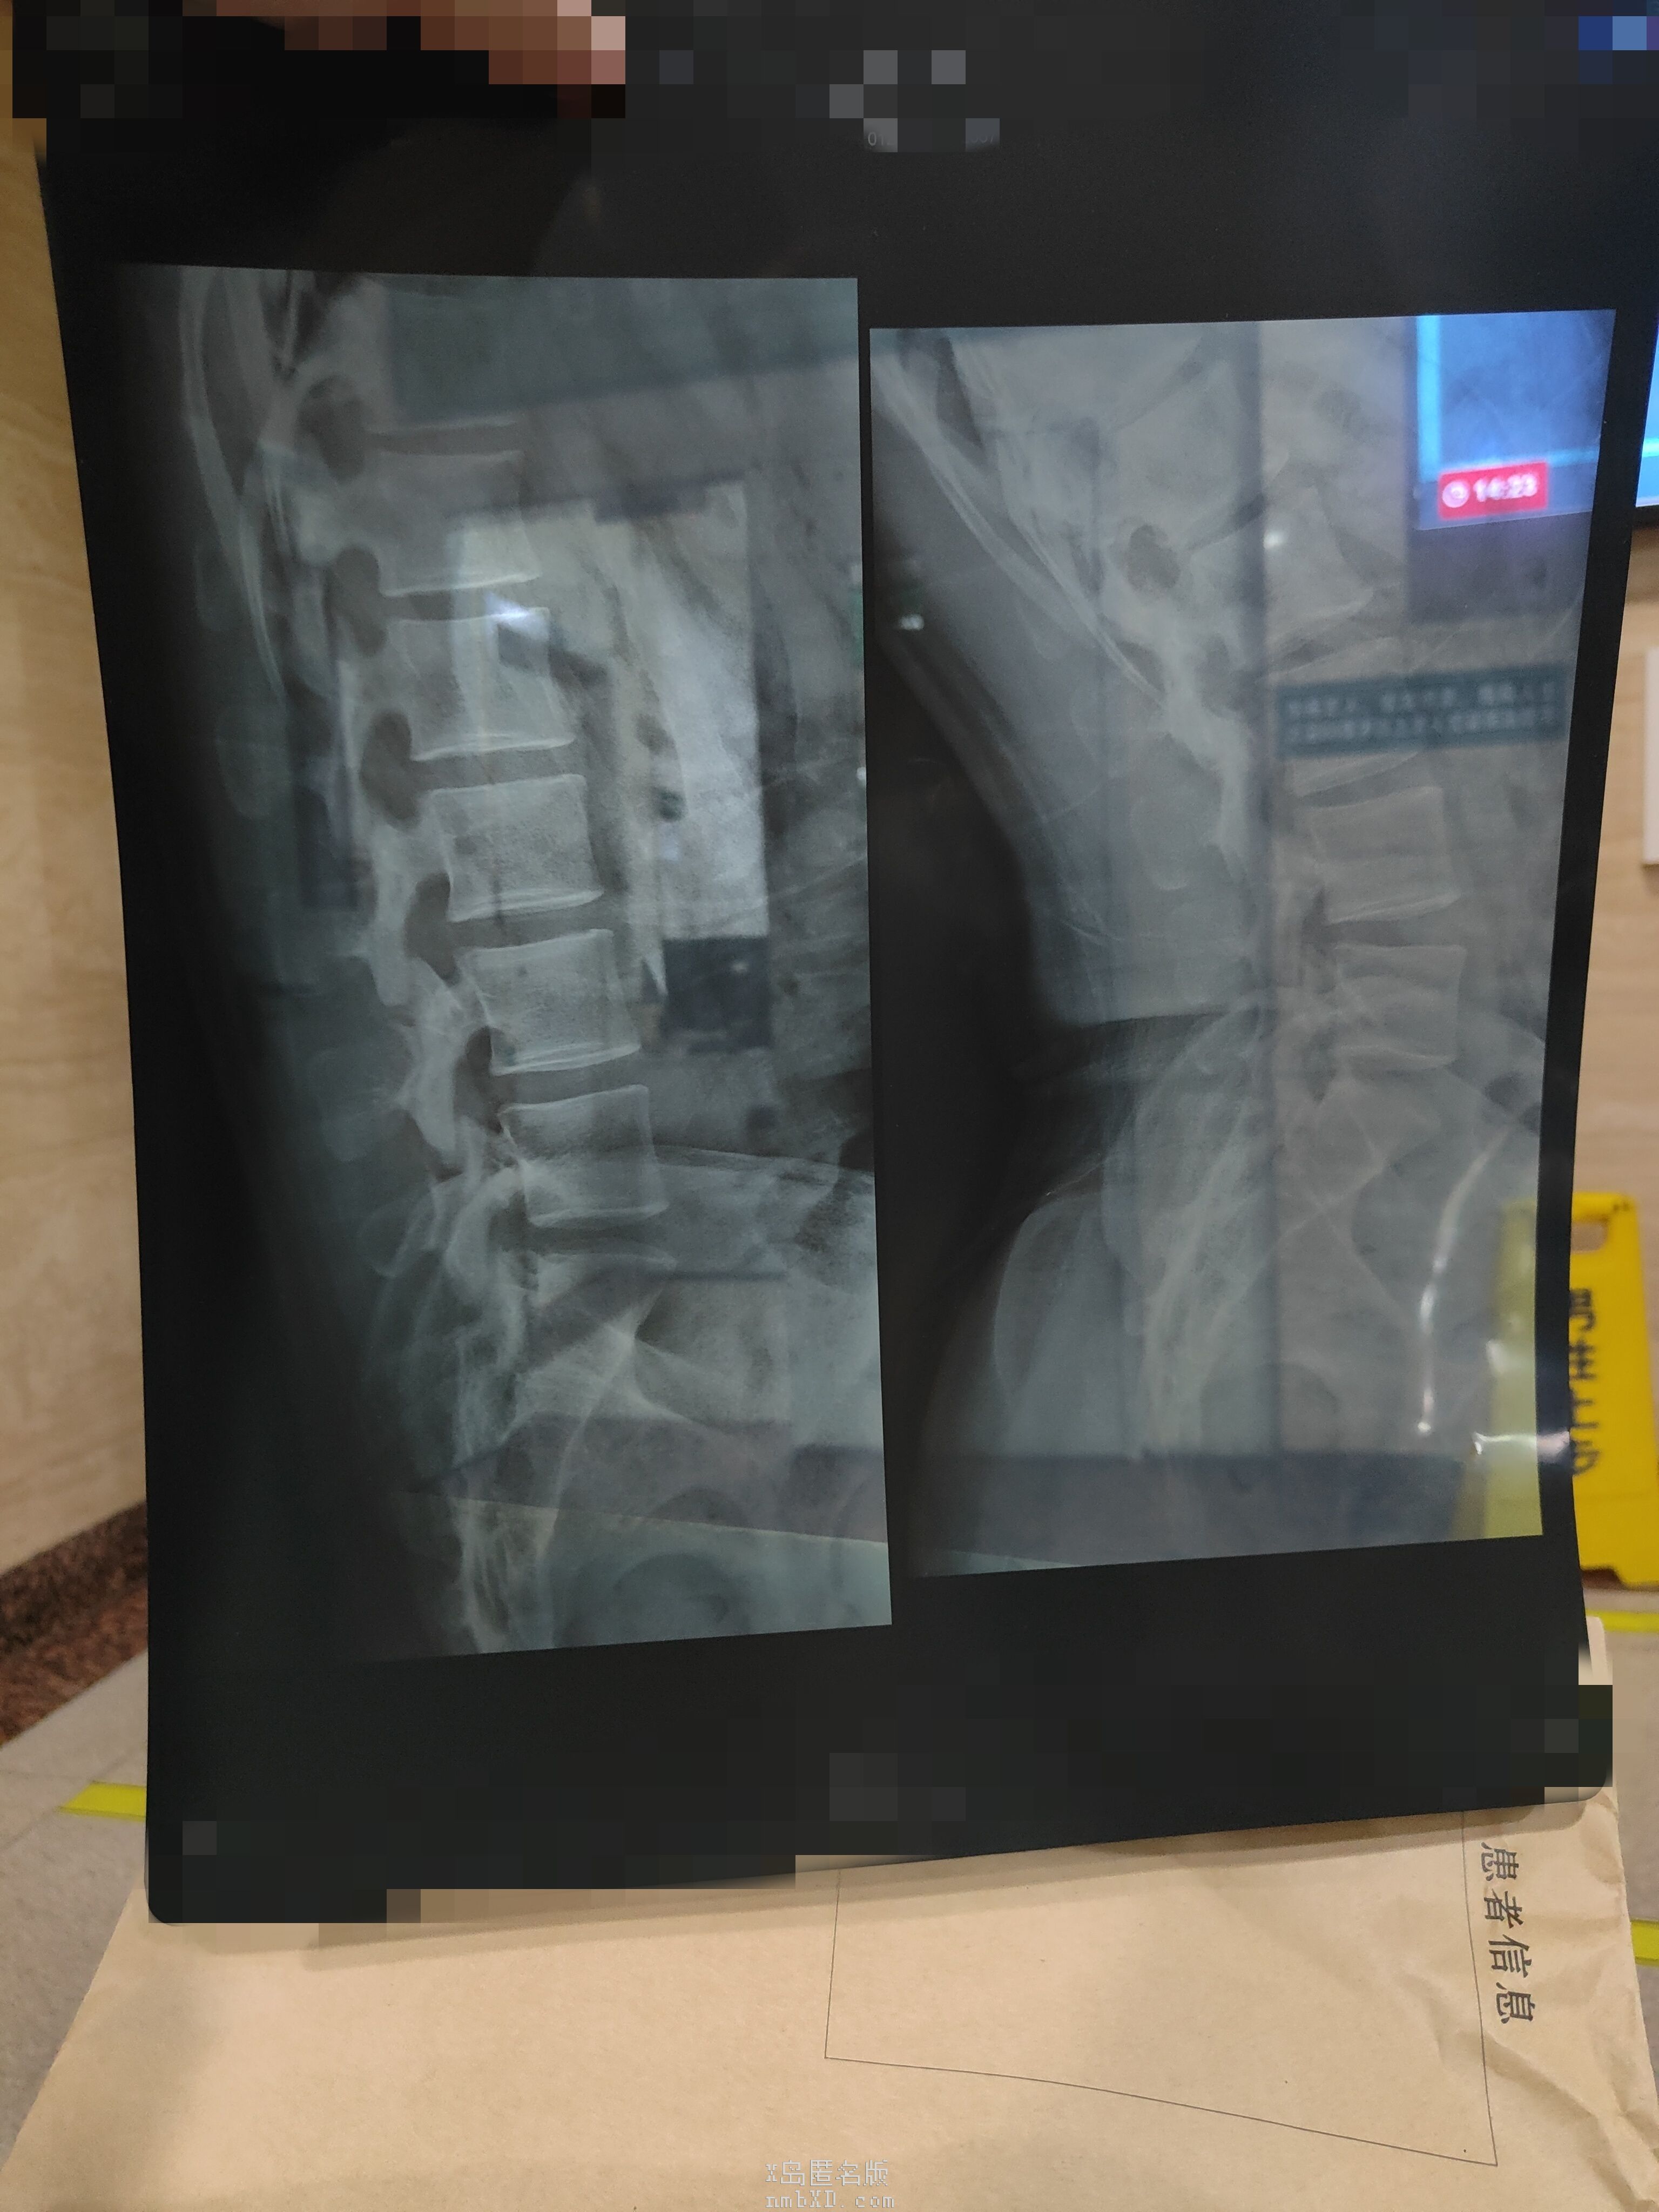

片子来力

收起 查看大图 向左旋转 向右旋转

有点点明显了已经,平常会不会下背痛,腰背累,晨僵之类的